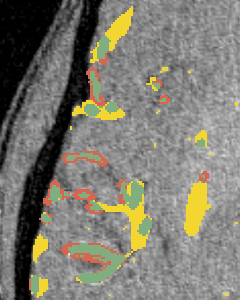

(a)

(b)

(c)

We perform three experiments to evaluate our method. (1) We compare the performance of our approach with commonly used unsupervised methods for vessel segmentation: Frangi [7], Sato [20], Hybrid Hessian [14] and Meijering [13] filters on four 2D datasets and two 3D datasets, all of which are publicly available. (2) We study the efficiency of learned representation for the downstream vessel segmentation task. To do that, we compare our method with existing self-supervised methods. (3) We examine the efficacy of the bifurcation loss in segmenting the regions around bifurcation points in 2D compared to methods which do not consider bifurcations.

Since our method is learning based, it can learn feature representations that are essential for vessel detection. This section compares the efficacy of the representation from different self-supervised tasks onto a downstream supervised vessel segmentation task. We compare our model with four self-supervision baselines, namely, context-encoder [17], image-denoising [24], image-colorization [26] and Models Genesis [27]. First, we train multiple networks using different pretext tasks on the DRIVE dataset. These networks are then finetuned on a supervised vessel segmentation task on the STARE dataset. We consider a limited-data and a high-data scenario, where finetuning is done with only 4 and 16 images respectively. Figure 2(a,b) show the training dynamics in both cases. Our method takes fewer iterations to converge compared to the other methods and achieves the best validation dice score.

3.3 Segmentation around Bifurcation Points (BPs)

(d)

(e)

In this experiment, we demonstrate the importance of our predicted bifurcation flow fields () in vessel-segmentation performance around BPs. To quantitatively measure the segmentation, we manually annotated bounding boxes (BBs) at multiple bifurcation regions in the DRIVE dataset. We performed an ablation study, where we didn’t consider bifurcation loss (BL) in our final formulation. Figure 2(c) reports the accuracy of identifying vessel pixels within the extracted BBs. Our proposed bifurcation loss significantly improves the segmentation at regions around BPs.